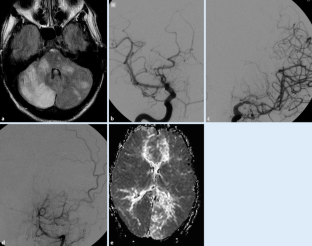

Abb. 1